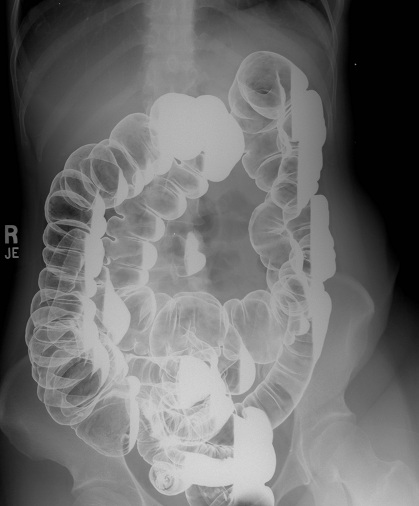

Fluoroscopy - Contrast Enema

Fluoroscopy is a study of moving body structures--similar to an X-ray "movie." A continuous X-ray beam is passed through the body part being examined. The beam is transmitted to a TV-like monitor so that the body part and its motion can be seen in detail. Fluoroscopy, as an imaging tool, enables physicians to look at many body systems, including the skeletal, digestive, urinary, respiratory, and reproductive systems.

A contrast enema is a lower gastrointestinal exam that uses x-rays to view the large intestine. There are two types of tests: the single contrast technique, where contrast is injected into the rectum to gain a profile view of the large intestine, and the double-contrast technique, where both air and contrast media are inserted into the rectum.

When you arrive, report to X-ray Central Reception (Area 4) or X-ray North. You will be asked to change into a hospital gown and to remove jewellery, dentures, glasses and any metal objects or clothing that might interfere with the x-ray images. You will then be called into the x-ray room and will be asked to lie down on the x-ray table. An image of your abdomen will be taken, and the radiologist will assess if the colon is adequately cleansed of stool. A well-lubricated tube is inserted into the rectum, and the bowels will be filled with contrast media. During this process, you must squeeze your buttocks together as much as you can, to prevent leakage.

After the intestines are filled, x-rays of the abdomen are taken, and this may be done in various table positions.